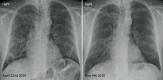

The potential mid-term and long-term consequences after severe acute respiratory syndrome coronavirus 2 (SARS-CoV-2) infections are as yet unknown. This is the first report of bronchoscopically verified organizing pneumonia as a complication of coronavirus disease 2019 (Covid19). It caused persisting dyspnea, impaired pulmonary function, and radiological abnormalities over 5 weeks after onset of symptoms. While organizing pneumonia frequently requires treatment with systemic corticosteroids, in this case it resolved spontaneously without treatment after 6 weeks. Healthcare professionals should consider organizing pneumonia in patients with persisting respiratory symptoms after Covid19.